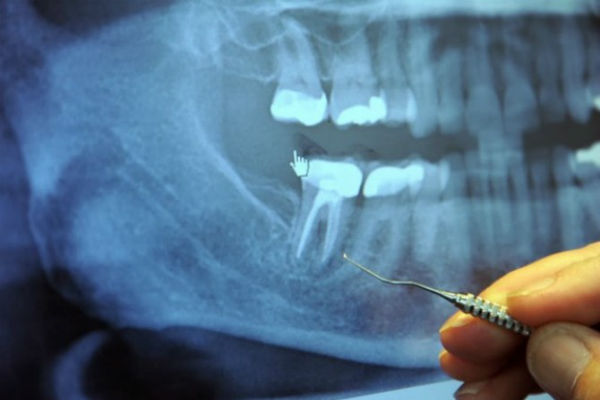

U pitanju je vađenje živca. Na milione ovih operacija se sprovede svake godine.

U sredini svakog zuba nalazi se zubna šupljina i u njoj pulpa, koja povezuje krvne sudove i nerve. Oko zubne šupljine se nalazi dentin, koji je sačinjen od živih ćelija koje luče tvrdu mineralnu supstancu. Spoljašnji dio zuba naziva se enamel i on okružuje dentin.

Korijeni svakog zuba dopiru do vilice i ostaju na svom mjestu zahvaljujući peridontalnom ligamentu. Stomatologe u školi uče da svaki zub ima 1-4 veća kanala. Međutim, postoji gomila kanala koja se uopšte ne pominje.

Svaki zub ima čitav lavirint sitnih cjevčica koje bi, kad bi se razmotale, bile dužine oko nekoliko kilometara. Veston Prajs je identifikovao 75 odvojenih pristupnih kanala u jednom centralnom sjekutiću.

Kad zubar izvede operaciju vađenja živaca, on probuši zub, a zatim ispuni šupljinu supstancom koja odsijeca dotok krvi do zuba, tako da ona više ne može da cirkuliše kroz zub. Međutim, lavirint cijevčica i dalje ostaje tamo, a bakterije, koje više nemaju svoj izvor hrane, kriju se u ovim tunelima gdje su bezbjedne od antibiotika i imune odbrane organizma.